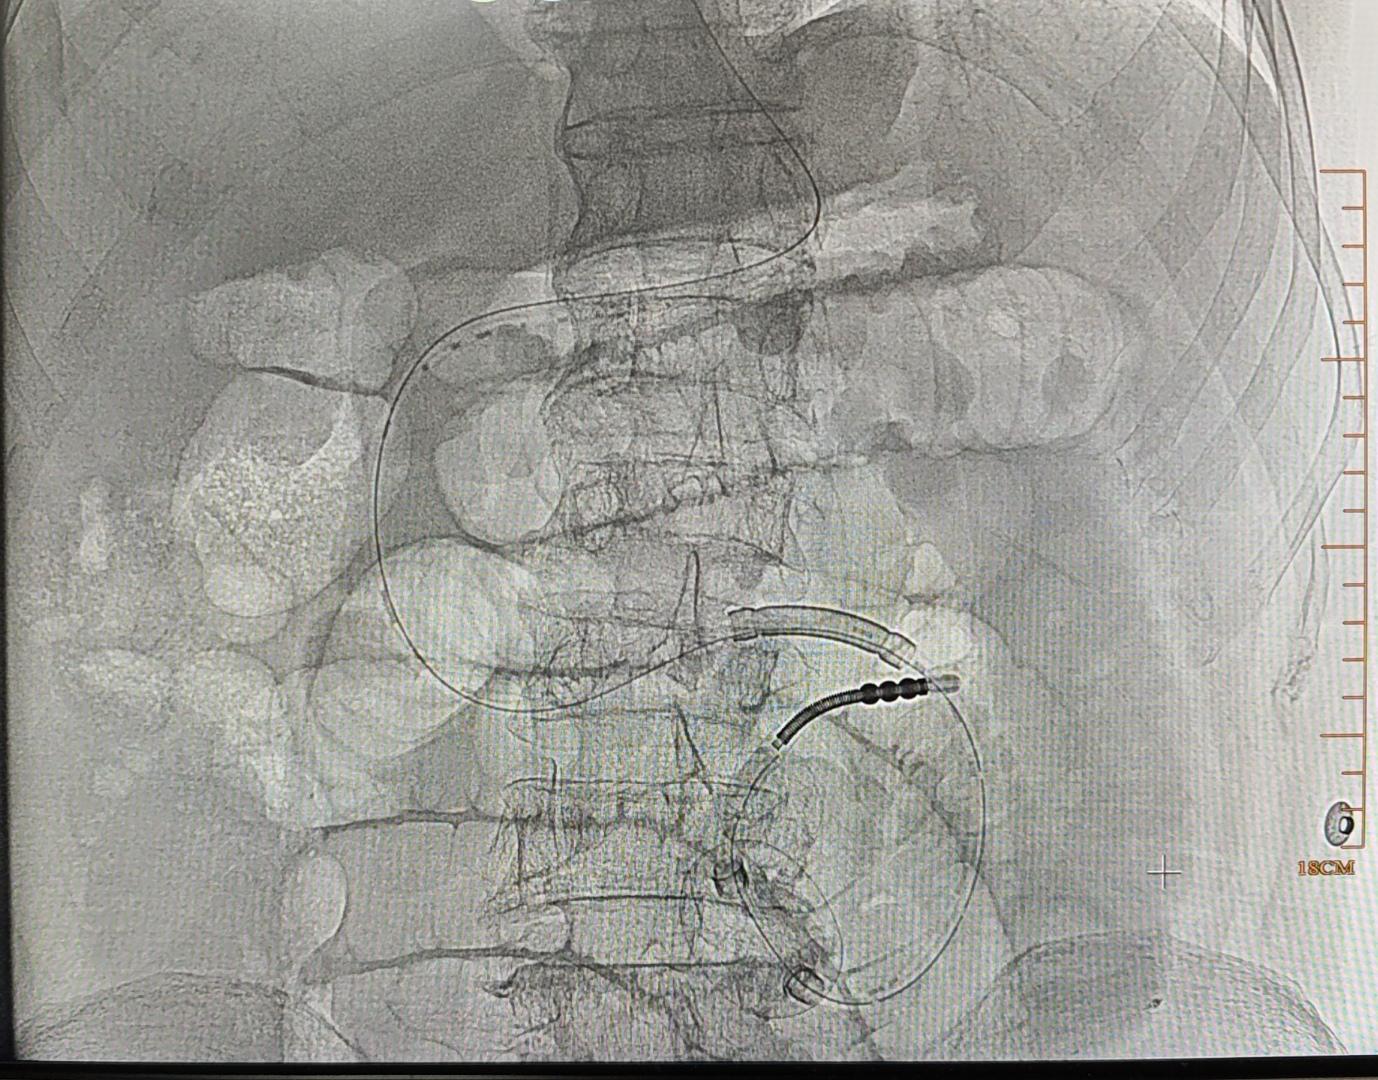

这周急诊有点多,连续4天都有急诊,今天特别多,今天出差下午三点回来,接连来了5台急诊,髂窝脓肿置管引流,胰腺炎伴脓肿引流管堵塞更换,肠梗阻导管植入,肺癌咯血介入治疗,肺部重症感染合并咯血介入治疗。虽然很累,又和女儿食言,但看到介入微创治疗能解决患者问题,缓解患者病痛,也还是很开心的[呲牙][呲牙][呲牙]

急诊咯血介入治疗,胸上动脉,锁骨下动脉分支,右侧支肋共干支气管动脉,右侧支气管动脉,食管固有动脉,左侧支气管动脉,右侧膈动脉,术前CTA以及选择合适的大导管和微导管真的重要,不仅能超选到位,又能快速完成超选。